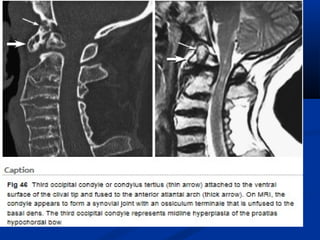

Condylus Tertius

Anomalies and malformations of the most caudal of the occipital

sclerotomes are collectively termed ‘ ‘manifestations of occipital vertebrae”

When the hypochordal bow of the fourth occipital sclerotome (proatlas)

persists or when the proatlas fails to integrate, an ossifled

remnant may be present at the distal end of the clivus, called the condylus

tertius or third occipital condyle .

This third condyle may form a joint or pseudojoint with the

odontoid process or with the anterior arch of the atlas and may lead to

limitation in the

range of motion of the CVJ .

There is an increased prevalence of os odontoideum associated

with this abnormality

Condylus tertius and platybasia. Midsagittal Ti-weighted MR image reveals

marked skull base flattening, with a Welcher basal angle of 150 dotted line). Note the

marked bowstring deformity of the cervicomedullary junction.

The C-1 arch (A) lies directly above the tip of the odontoid process (0). Marrow within

accessory ossification centers (condylus tertius)